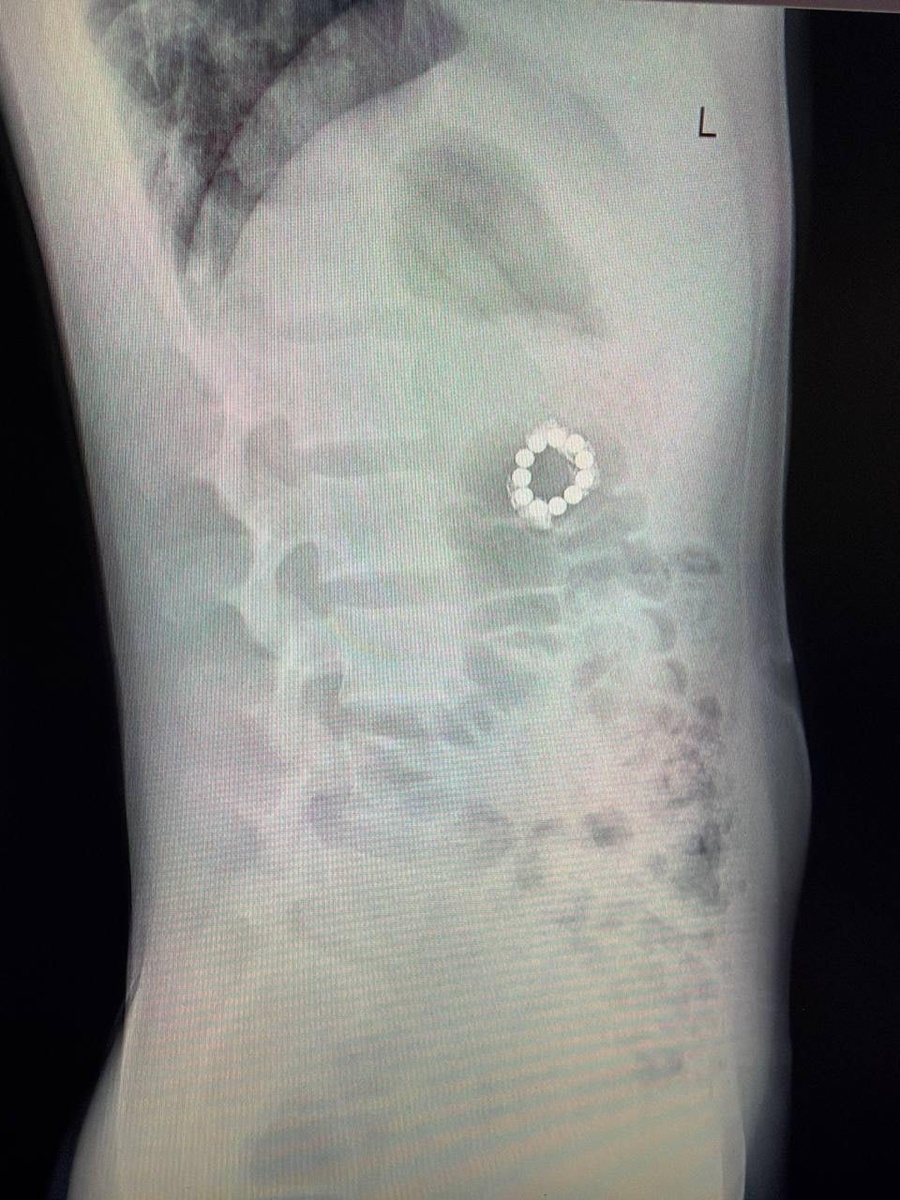

11-летний мальчик пришёл к врачу с болью в спине после тренировки, а ушёл с диагнозом "11 магнитов в желудке". Оказалось, он проглотил их из любопытства, а потом боялся признаться в этом родителям.

Когда боли в животе и рвота стали невыносимыми, подростка отправили на КТ. Врачи обнаружили в желудке и кишечнике целый "набор" магнитов, которые за годы сцепились, пробили стенки органов и нарушили кровоснабжение.

Хирурги Центра Рошаля извлекли все 11 магнитов – сначала семь, потом ещё четыре.